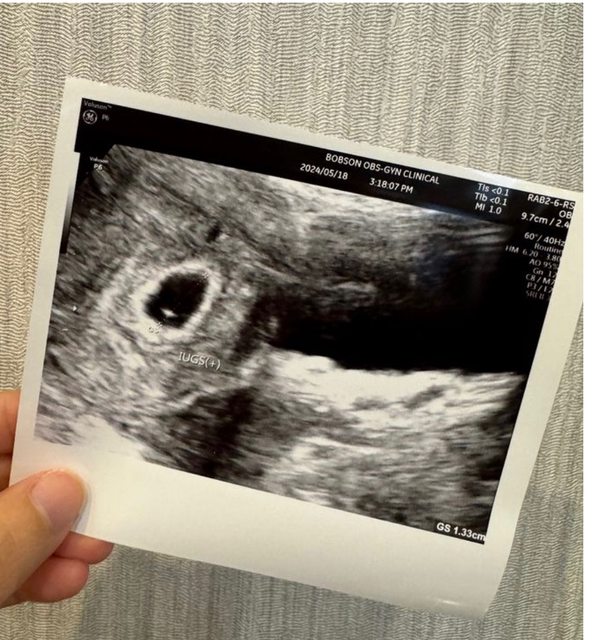

各位爸爸媽媽好, 我上一次月經第一天是3/25, 5/4去照超音波看到約0.56的胚囊, 5/18去照超音波看到約1.33的胚囊,但還沒看到胚胎,按照孕期計算這週應該是第七週, 但醫生說可能才五週多一點,醫生說下週一定要看到胚胎。 請問爸爸媽媽誤差的兩週是正常嗎, 我好緊張喔QQ https://i.imgur.com/86HaV2s.jpeg

n870881 : 我第一次照也是誤差約兩週喔 過兩週照到心跳就校正 05/22 19:57

n870881 : 回歸了 現在10週了寶寶很健康~ 05/22 19:57

lalatwo : 我第二次看診也是應該8週但照出來才6週,後來一週後 05/22 20:08

lalatwo : 回診照到,後續大小也慢慢追上,目前13週已經跟app 05/22 20:08

lalatwo : 推估時間一樣 05/22 20:08

qiori : 我第一胎也是差兩週,醫生說就比較晚受孕而已,小 05/22 22:35

qiori : 孩都已經6歲,放鬆心情吧 05/22 22:35

jplix : 我跟妳的情況很像 實際胚胎大小晚兩週喔 05/23 12:08